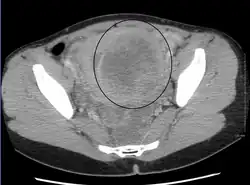

A relatively large submucosal leiomyoma; it fills out the major part of the endometrial cavity. -